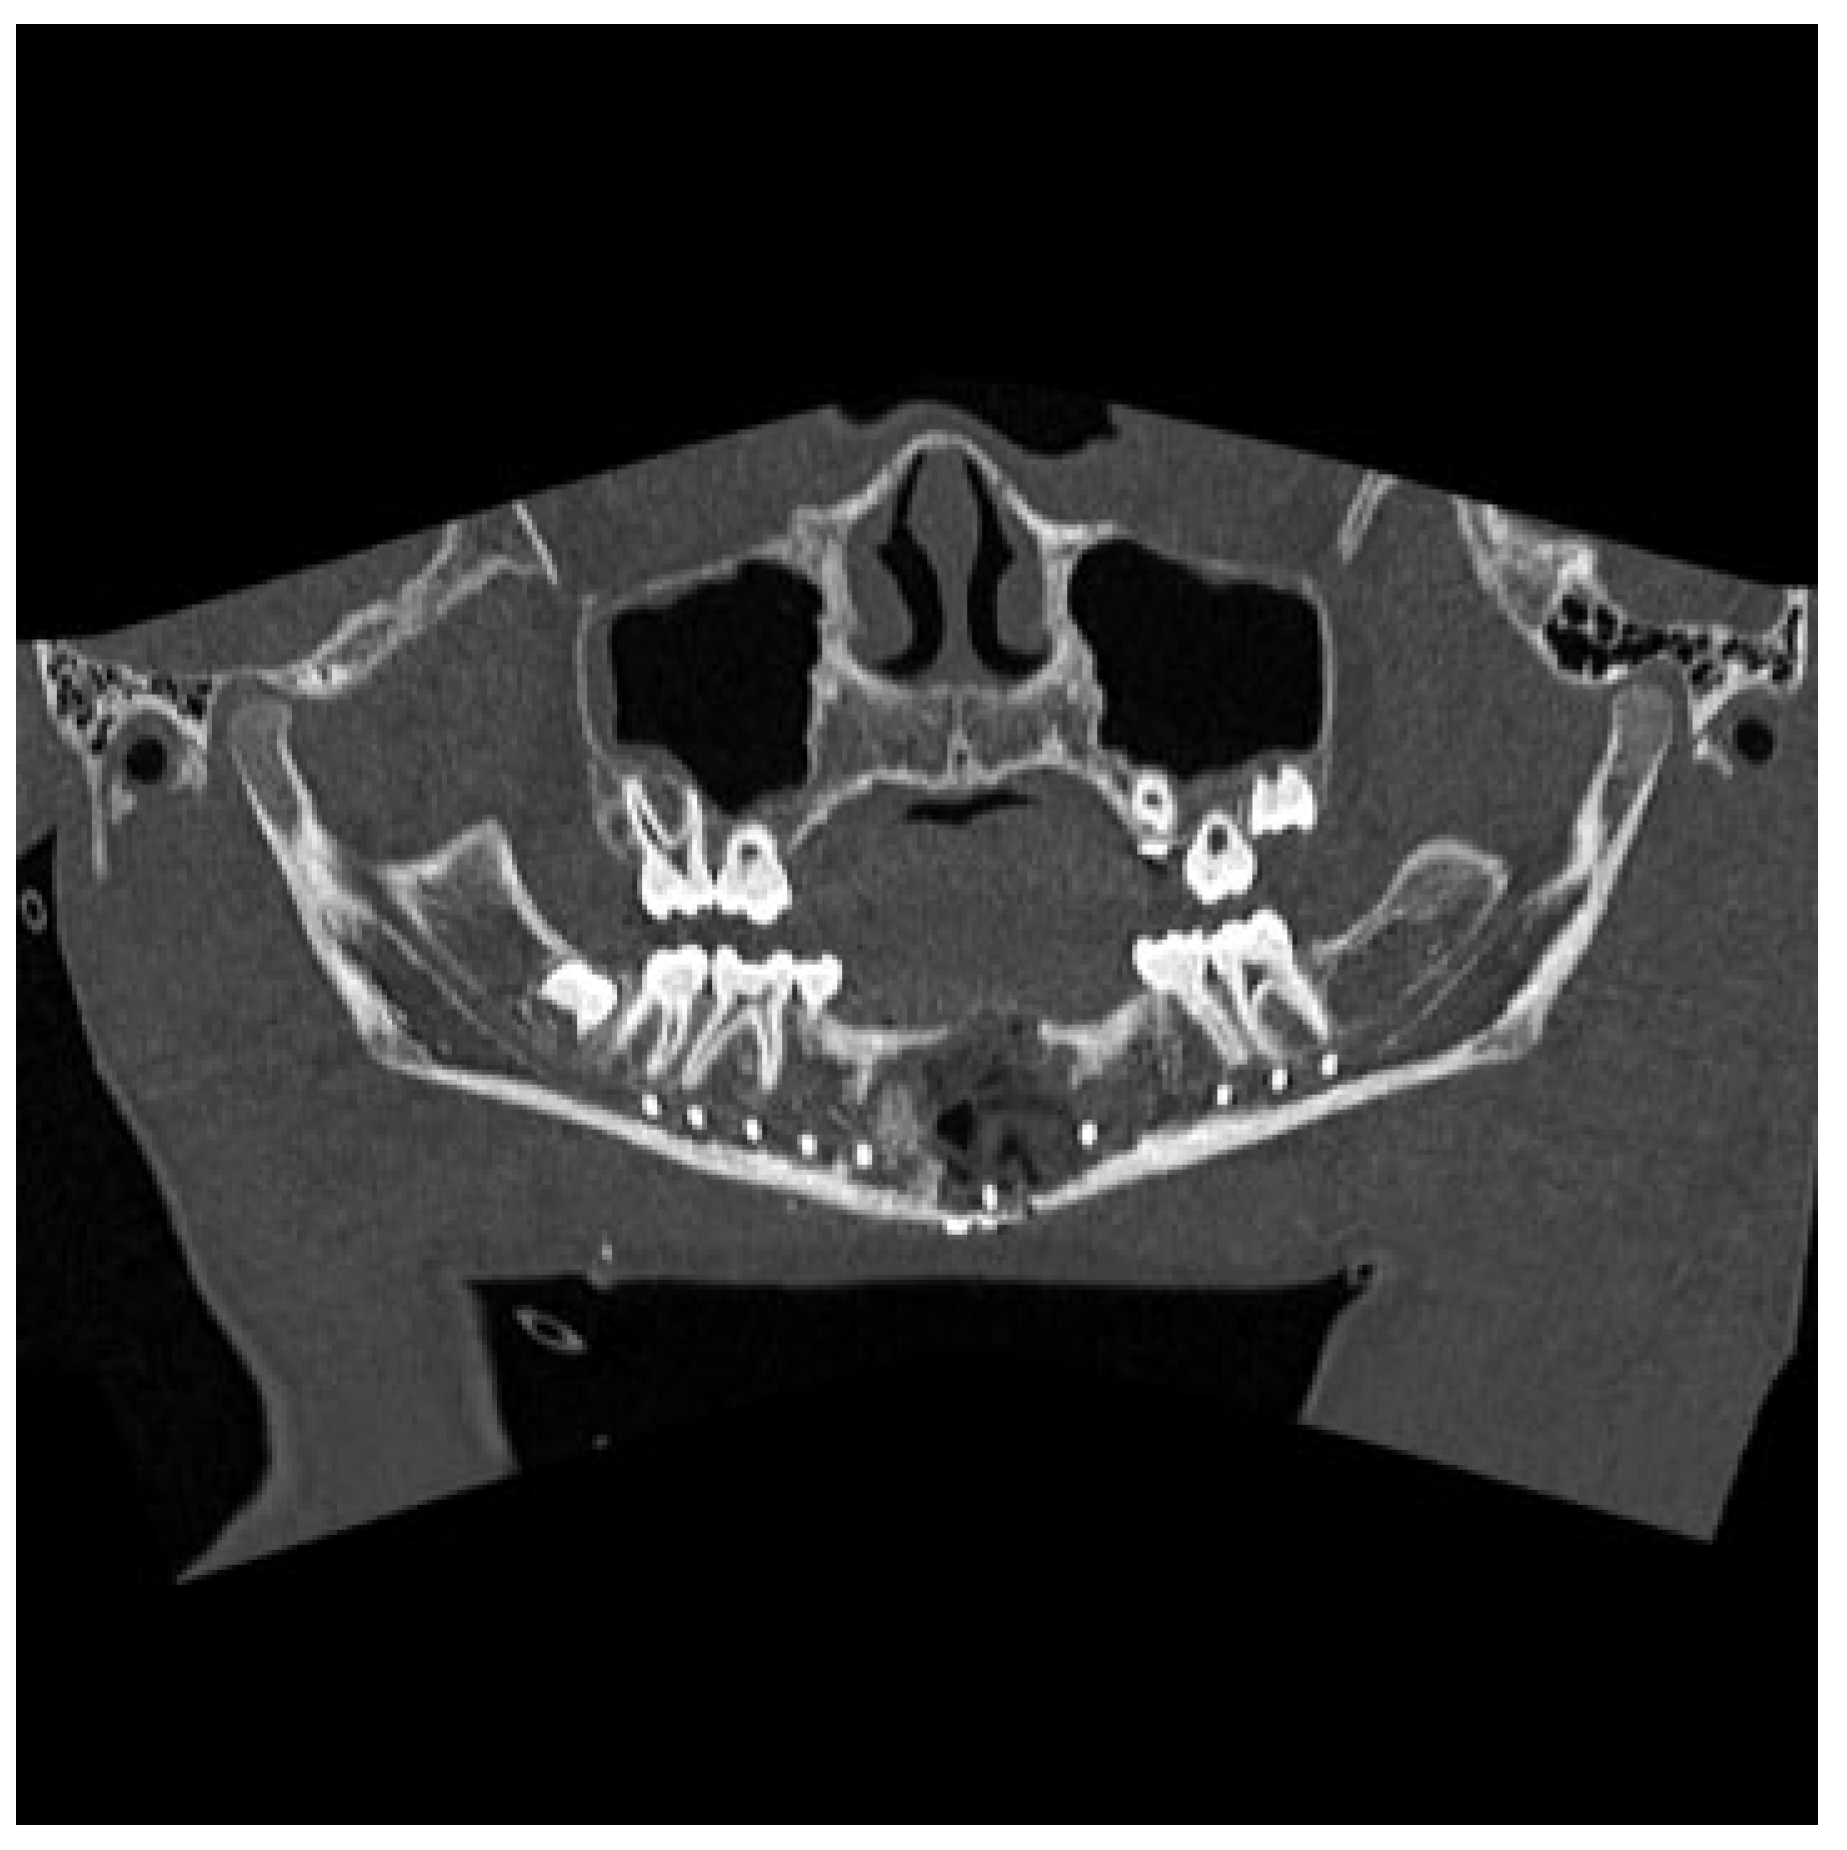

Figure 5.

Panorex computed tomography scan obtained 7 weeks postoperatively demonstrating improved anatomic alignment with some neo-osteogenesis and persistent cystic defect of the mandible.